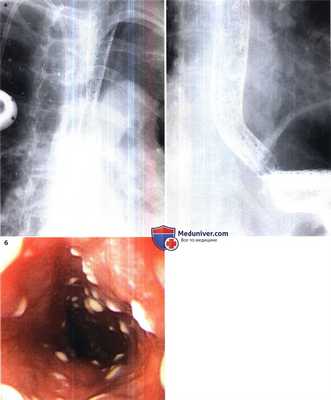

Кандидозный эзофагит.

При компьютерной томографии отмечается однотипное поперечное утолщение стенок пищевода более 5 мм.

При контрастировании отмечается симптом «мишени» — на фоне отека стенка слизистой оболочки выглядит гиподенсной (стрелка).

Эзофагит, вызванный грибами рода Candida у мужчины 73 лет.

(а) При рентгенографии с двойным контрастированием выявлена диффузная бугристость пищевода.

(б) При эндоскопии обнаружены множественные беловатые бляшки.